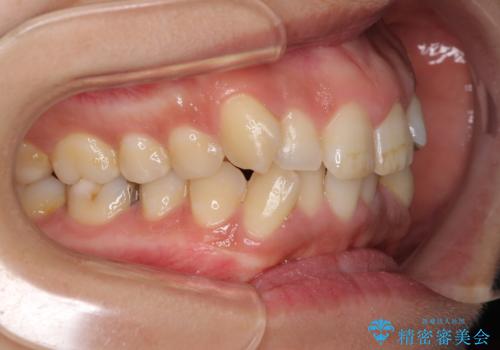

- 上下前歯のデコボコを気にして来院された患者様です。

デコボコが強いため、非抜歯で矯正をすると出っ歯仕上がりとなるため、上下左右の第一小臼歯4本を抜歯することとしました。